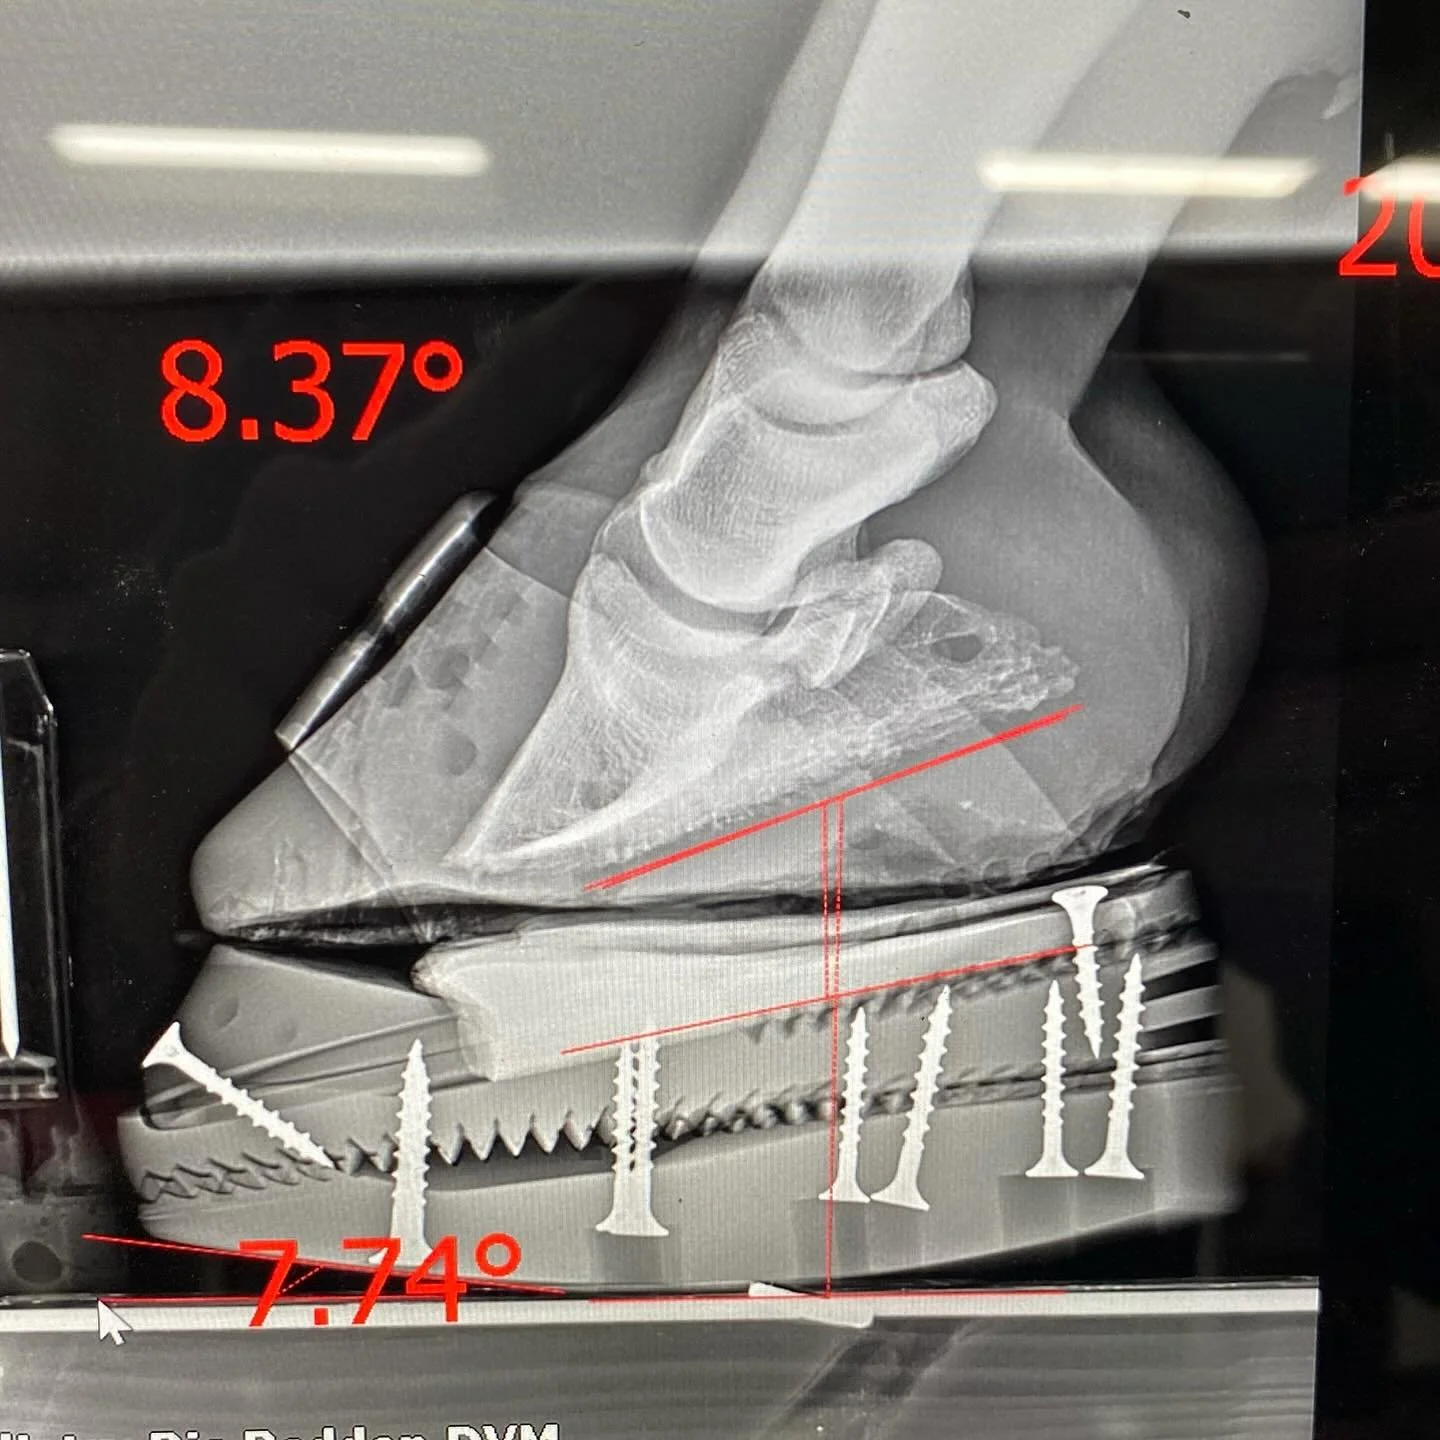

Está capacitado para interpretar radiografías y venogramas del casco, evaluando estructuras óseas, cápsula solar, espacio vascular y tejidos internos.

Internado uno a uno durante tres meses en el International Equine Podiatry Center (IEPC) junto al Dr. Ric Redden, considerado el padre a nivel mundial de la podología equina y fundador de NANRIC, marca de referencia en herraduras terapéuticas. Formación avanzada en herraje mecánico, interpretación de radiografías y venogramas y en el tratamiento de casos complejos como laminitis, síndrome navicular, talones colapsados, caballos topinos y numerosas patologías.

x2 Dr. Ric Redden’s Equine Podiatry Course

x2 Curso intensivo de Podología Equina impartido por el Dr. Ric Redden, referente mundial en el tratamiento de patologías del casco. Un enfoque práctico y avanzado para comprender la biomecánica, diagnosticar correctamente y aplicar técnicas efectivas en casos complejos como laminitis, deformidades o cojeras crónicas.

Internado uno a uno de tres meses junto al Dr. Ric Redden, considerado el padre de la podología equina a nivel mundial y fundador de NANRIC, marca de referencia en herraduras terapéuticas. Formación avanzada herraje mecánico, en interpretación de radiografías y venogramas y en el tratamiento de casos complejos como laminitis y otras patologías.